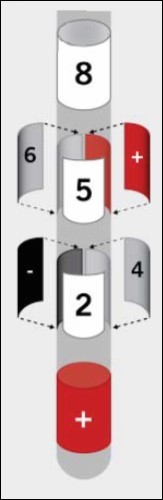

Microelectrode mapping was done with three electrodes. Test stimulation was performed to verify correct placement and define the therapeutic window (TW). Once desired position depth was reached at the central part of the STN, the stylets were replaced with segmented DBS electrodes The right STN stimulation was started at -5mm from the target point. At -4mm anterior and central a sufficient stimulation effect was seen. Sufficient stimulation could be continued till +1.5mm. At the target point sufficient stimulation was seen in all three microelectrodes. A sufficient reduction of rigor and tremor in the neurological examination was seen with 2mA. The segmented electrode tip (2 and 3), (Figure 1) was positioned at +1.5mm over the target point.

Figure 1.This model shows the segmented electrode with its segmented middle segments and multiple, activatable contact panels for adjusted stimulation.